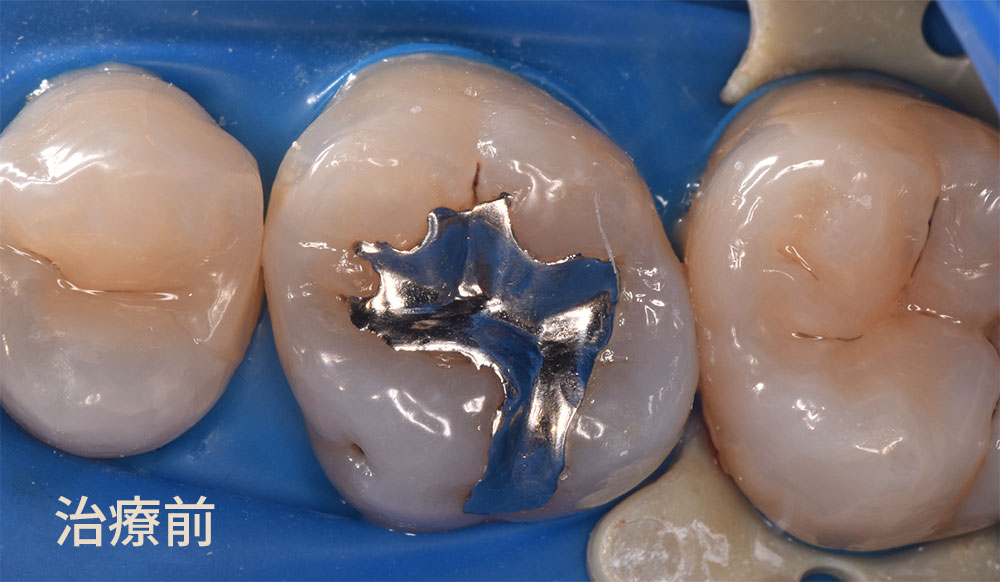

実際に銀歯の中を外してみると、そこには虫歯がありました。

上の写真の茶色の箇所が虫歯でした(赤い矢印)。銀歯の隙間から新たに虫歯になっていました。マイクロスコープを用いて虫歯を的確に除去しました。写真で見ていただいている歯を取り囲むブルーの部分は、ラバーダム防湿と言います。